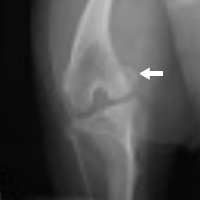

膝蓋骨内方脱臼のレントゲン(右後肢) |